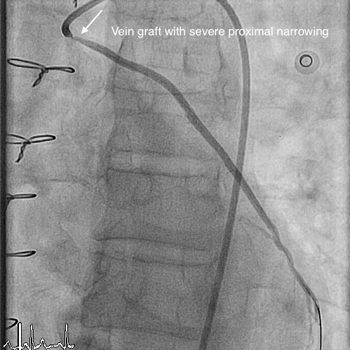

Vein graft (SVG) stenting

Vein graft (SVG)…

Learn more